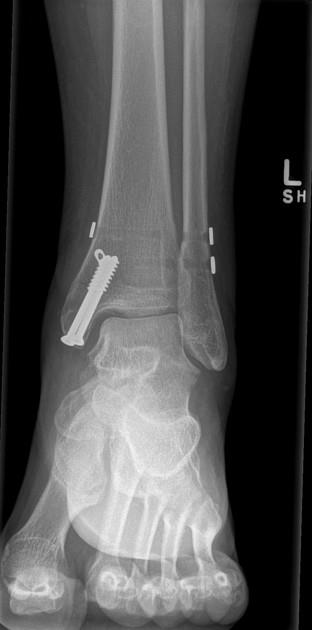

Syndesmosis TightRope® XP Implant System

• Indications

• Provide fixation during the healing process following a syndesmotic trauma

• Fixation of syndesmosis (syndesmosis disruptions) in connection with Weber B and C ankle fracture

• The syndesmosis should be formally reduced prior to fixation and confirmed using fluoroscopy, direct visualization during open reduction, or both based on surgeon preference and severity of injury